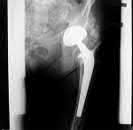

What is the most likely mechanism of failure for the patellar component shown: